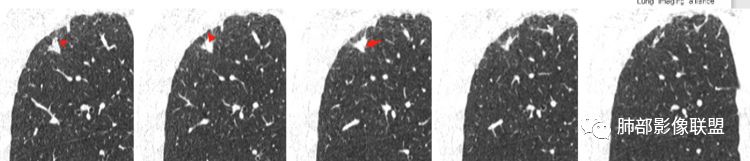

2.右肺上叶胸膜下不规则实性密度小结节影,密度均匀。边界清楚,缺乏典型深分叶,除个别层面上圆隆外,大多边缘平直甚至内凹,成三角形轮廓,冠状位甚至状如“奔驰”车标。

3.可见棘状突起或条索影牵于胸膜间,胸膜侧可见毛刺。灶周未见磨玻璃影。

4.周围肺组织见小结节影,胸膜多见结节样增厚。

棘状突起——小病灶边界清楚,棘状突起或长条索影,如果是炎性,时间够漫长。

相邻胸膜增厚——周围肺组织小结节影,肺尖胸膜结节样增厚,范围较广,支持慢性病灶。